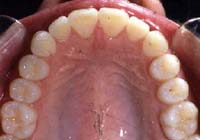

Treatment Time: 8 months

Aligners: 13 Upper, 13 Lower